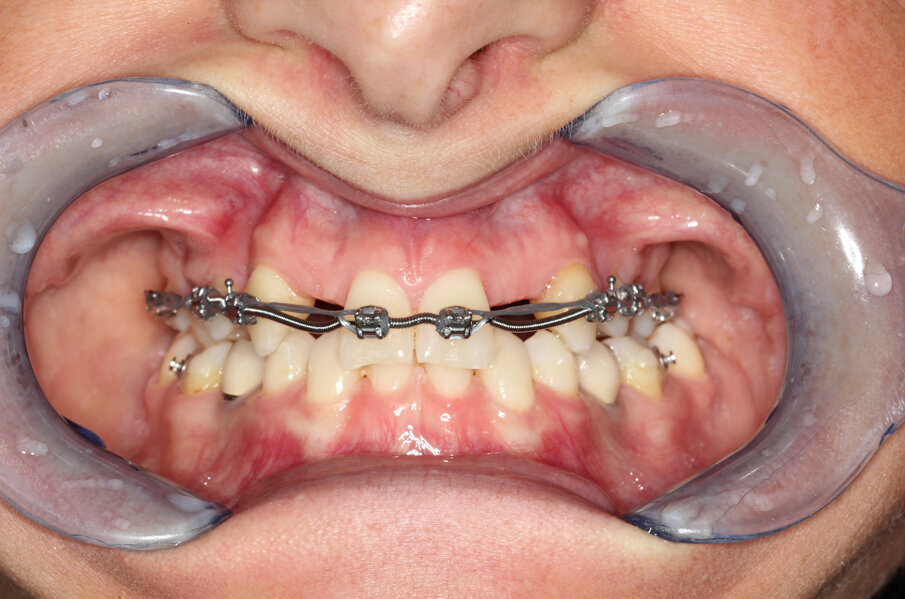

Om de behandeling niet nodeloos ingewikkeld te maken, is een set-up gemaakt waarin is gekeken of we met een restauratief/orthodontisch behandelplan uit de voeten kunnen om zo orthognatische chirurgie te vermijden. Er werd een wax-up gemaakt en deze werd met Luxatemp gepast bij de patiënte om te beoordelen of we dimensionaal goed zouden uitkomen. Deze mock-up werd ook gemaakt om patiënte te laten zien welk uiteindelijk esthetisch resultaat we zouden kunnen benaderen (afbeelding 3 en 4).

In samenspraak met de patiënte en in goed overleg met de behandelend orthodontist werd besloten de implantaten op de posities 13 en 23 te verwijderen, de cuspidaten naar distaal te verplaatsen en de angulatie van de elementen te corrigeren, zodat het plaatsen van twee implantaten op de posities van de laterale incisieven goed mogelijk zou worden (afbeelding 5 en 6).